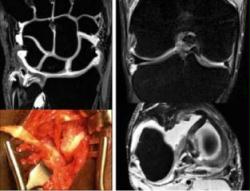

"Radiologie pédiatrique - Advances in Pediatric Radiology - Expertise from the Children Hospital in Philadelphia (CHOP)"

Samedi 6 septembre 2014 - 8h15-13h

Auditoire Jéquier Doge, PMU, CHUV, Lausanne

Dr Leonor ALAMAO & Pr François GUDINCHET

- Programme (pdf)